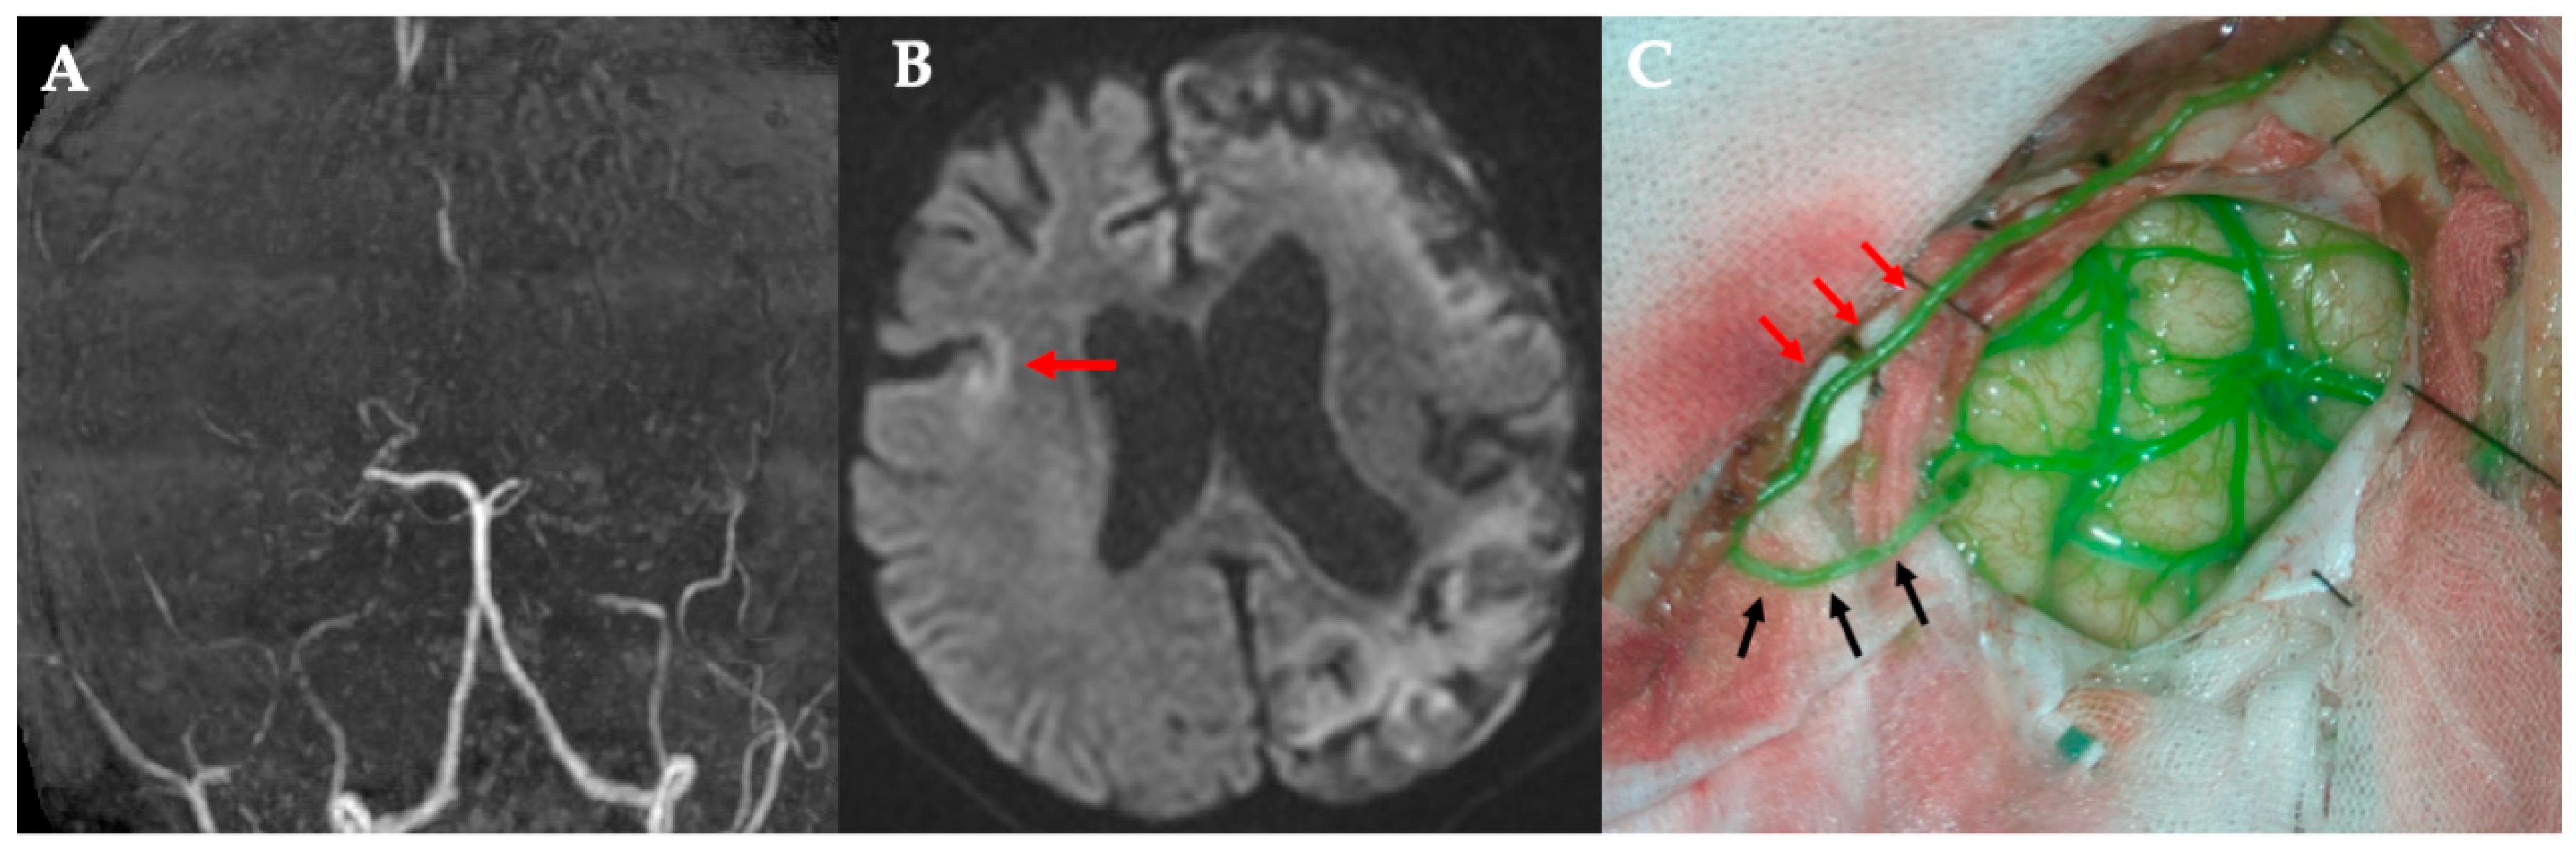

All five procedures were technically successful. Table 1 summarizes the key characteristics of each case. Preserving a side branch added an average of 5.6 min to the procedure (range, 3–11 min). In all cases, the bypass was patent on intraoperative ICG angiography, which demonstrated immediate perfusion of the distal MCA territory through the graft (Figure 2 and Figure 3). A schematic of this procedure is shown in Figure 4. The caliber of the STA side-branch donors ranged from approximately 0.5 mm to 1.1 mm (mean: 0.88 mm), closely matching the recipient artery diameters (0.4–0.9 mm, mean: 0.64 mm). No intraoperative complications (such as anastomotic thrombosis and vessel injury) occurred. The main STA trunk and any unused branches remained in situ to continue perfusing the scalp, and no signs of scalp ischemia were observed after sacrificing the side branch.

Figure 2. Case 1. (A) MRA. Poor delineation of bilateral internal carotid artery endings. (B) DWI. Right acute cerebral infarction. (C) Revascularization using the side of the STA parietal branch (black arrow). (D,E) The STA parietal branch main stem blood flow is preserved (red arrow), and the side branch (black arrow) is anastomosed to M4 in the frontal lobe. ICG showed patency of the bypass vessel (black arrow). MRA, magnetic resonance angiography; DWI, diffusion-weighted image; STA, superficial temporal artery; ICG, indocyanine green.